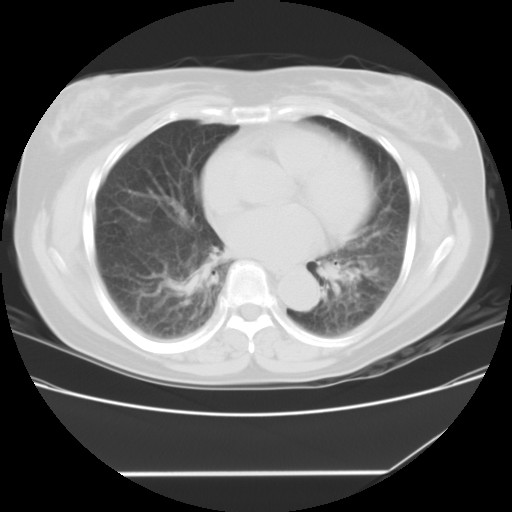

间质性肺炎,有纤维化趋势。

1)慢性支气管炎并肺部感染、肺气肿。2)肺间质纤维化。

间质性肺炎,左下肺机化性肺炎。